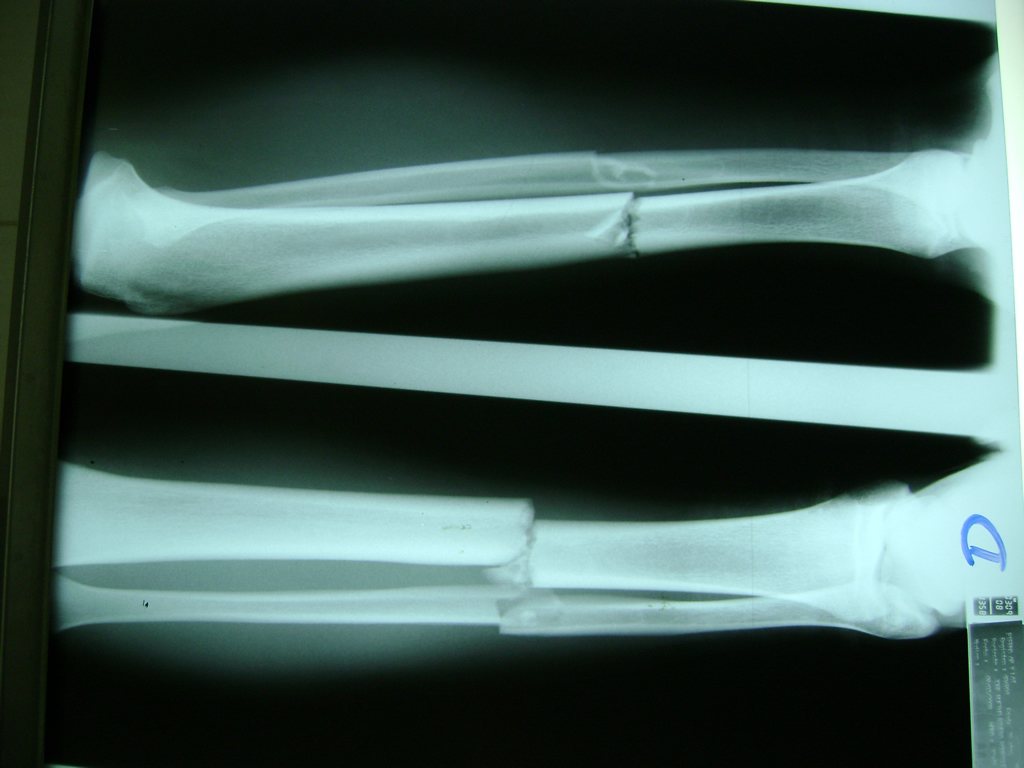

Aunque cada uno de estos huesos puede fracturarse por separado, normalmente la rotura es una lesión que se produce de forma conjunta

La mayor parte de las roturas implican a la parte proximal del hueso (parte del hueso próximo a la rodilla) o a la parte distal (parte del hueso cerca del tobillo).

Debido a la fina cobertura de piel que recubre la tibia y el peroné, las fracturas generalmente son abiertas, es decir, el hueso roto rasga la piel, atravesándola. Las fracturas de tibia y peroné generalmente se producen por un fuerte impacto o torsión.